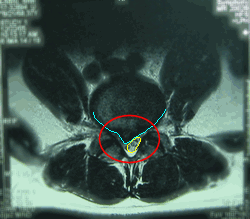

腰の骨ヘルニアのMRI断面画像

■水平断面

写真左(患者さん右)に飛び出して神経が圧迫されている状態が見られます。